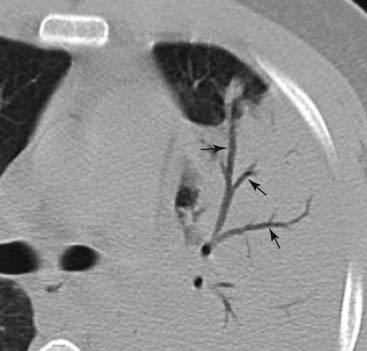

Figure 3-3 Air bronchograms demonstrated on CT scan.

Numerous black, branching structures (solid black arrows) represent air that is now visible inside the bronchi because the surrounding airspaces are filled with inflammatory exudate in this patient with an obstructive pneumonia from a bronchogenic carcinoma. Normally, on conventional radiographs, air inside bronchi is not visible because the bronchial walls are very thin, they contain air, and they are surrounded by air.